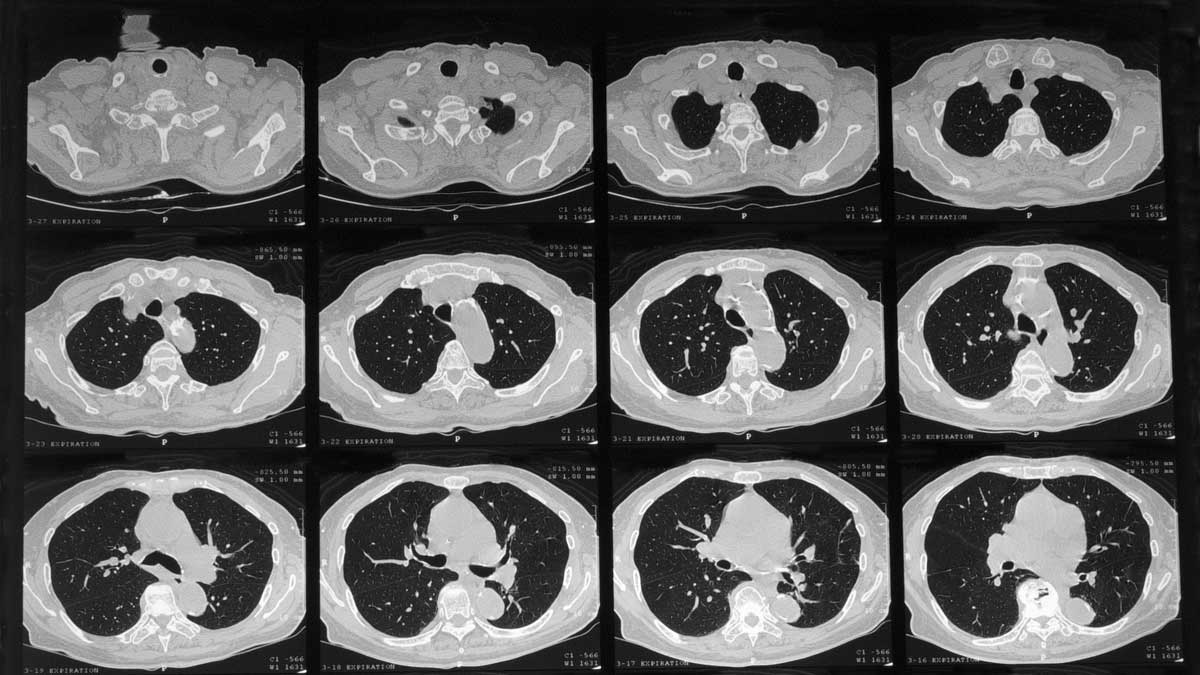

En spesiell CT-undersøkelse (HRCT) av lungene gir som regel det beste grunnlaget for å stille diagnosen lungefibrose. Enkelte ganger vil man likevel ta en vevsprøve fra lungene og undersøke denne i mikroskop.

Slik ser bildene ut når man tar en HRCT-undersøkelse.

Diagnose fra CT-undersøkelse

Ved å sammenholde resultatet fra HRCT og vevsundersøkelsen kan man i mange tilfeller finne ut hvilken type lungefibrose det dreier seg om. I de fleste tilfeller vil en trenet røntgenlege kunne gi en diagnose på bakgrunn av røntgenundersøkelsen alene.

Dette fordi røntgenundersøkelsene i dag etter hvert har fått svært god kvalitet og skarpe bilder med fine detaljer.